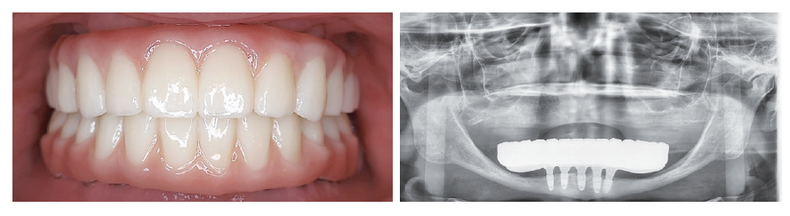

최근 내원 환자들의 골 상태는 점점 불리해지고 있으며, 단순 식립이 어려운 케이스가 증가하고 있다. 이러한 상황에서 가철성 보철로는 만족스러운 결과를 얻기 어렵고, 고정성 전악 보철, 특히 All-on-X 치료의 비중이 자연스럽게 높아지고 있다.

All-on-X 치료는 각도 식립, 즉시로딩, 그리고 보철의 정확성이 동시에 요구되는 술식이다. 이를 고려했을 때, 유지·관리와 Retribility가 뛰어난 cementless 보철 시스템은 선택이 아닌 필수라고 판단했다. 여러 시스템을 임상에 적용해 본 결과, FOXDEN 시스템은 국내 임상 환경에 사장 현실적인 대안이 될 수 있다고 느꼈다.

수술 후 Cuff를 선택해 Abutment를 연결하고 스캔바디 체결만으로 바로 디지털 인상이 가능하다. 즉시 디자인 후 3D 프린팅을 통해 임시 보철 제작이 가능해, 전악 수술 후 3시간 이내 즉시 로딩이 가능해졌다.

최근 이마고웍스의 AI 디자인 모듈(Roydent 제공)을 적용하면서 디자인 시간 또한 절반 이상 단축됐고, 현재는 전악 수술 후 1주 이내 지르코니아 최종 보철 완성까지 진행하고 있다.

All-on-X 치료에서 우리가 궁극적으로 추구하는 것은 단순한 고정이 아니라 정확한 Passive fit과 장기적인 안정성이다. FOXDEN의 Z-plus와 X Abutment는 Cementless 보철의 장점을 임상적으로 구현하면서, All-on-X와 Digital dentistry의 흐름에 가장 현실적인 해답을 제시하는 시스템이라 생각한다.